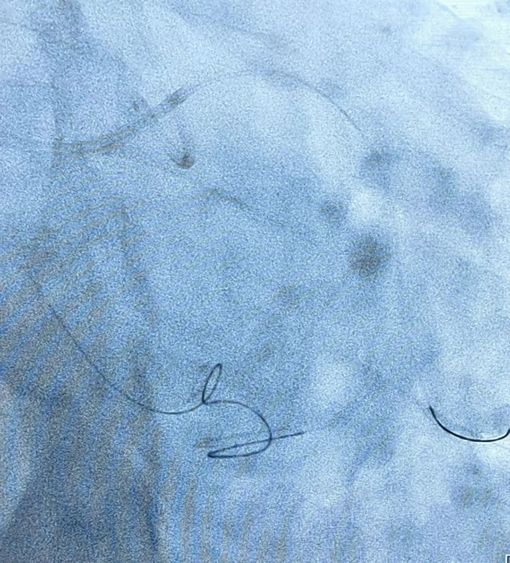

对于钙化、扭曲、血管走形不清的 CTO 血管段,反复尝试且逐步升级逆向导丝均不能通过闭塞段,为提高 CTO 段开通效率,术者巧妙使用导丝行 Knuckle 技术,通过推进 J 形结构的亲水导丝在内膜下空间进行钝性剥离,为下一步行 CART 技术提供支持。

通过严重迂曲心外膜通道的逆向导丝有了逆向导丝指引,术者再次尝试正向进入靶病变,应用 CART 技术,通过手感对斑块软硬程度的认知,经过延长导管与微导管配合,正向反复尝试、升级导丝,最终使用导丝正向通过夹层通路。正向导丝与逆向导丝慢慢会师,双向导丝交汇,多体位证实导丝无限接近。继续操作正向导丝缓慢前行,顺利进入逆向微导管内,并送入 AV 支。